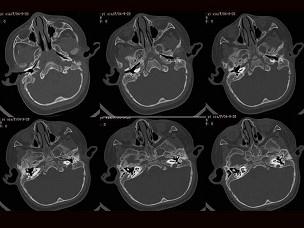

问题 女,2岁,两侧耳廓发育不对称,左侧听力差,如图所示,最可能的诊断为?(?)

选项 A.左侧外耳道闭锁 B.左侧中耳炎 C.左侧内耳道畸形 D.左侧胆脂瘤 E.左侧中耳炎胆脂瘤形成

答案 A